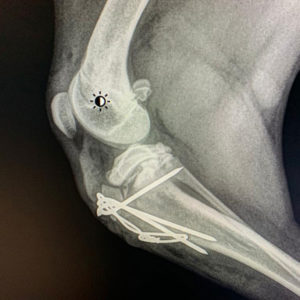

A ZAMBRA la recogimos del CPA con una avulsión de tuberosidad tibial en la pata derecha trasera. Ya esta operada y recuperándose perfectamente, aunque cuesta que haga reposo porque todo lo que quiere es jugar y pasarlo bien. Una perrita de personalidad abierta. Cariñosa y muy agradecida. Sumisa con las personas.